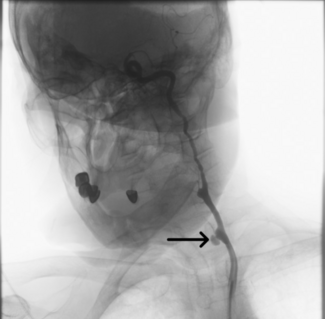

A 59-year-old man with exertional angina and coronary angiography showing chronic total occlusion of the right coronary artery with collateral filling from the left anterior descending artery. Dual injection revealed an ambiguous proximal...